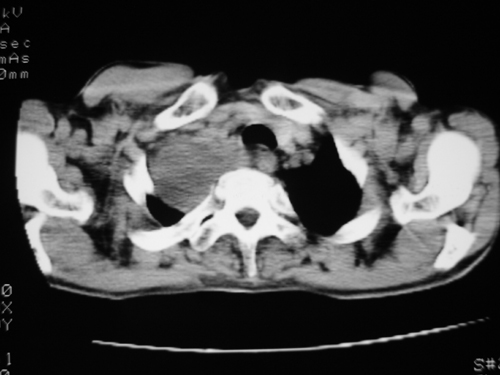

以下是引用yangyudong333在2008-4-29 5:46:00的发言:[br]1左上叶结节呈分叶状,边缘毛刺,考虑肺癌并纵隔淋巴结转移可能性大,结核待排,[br] [br]2右侧多发包裹性胸腔积液